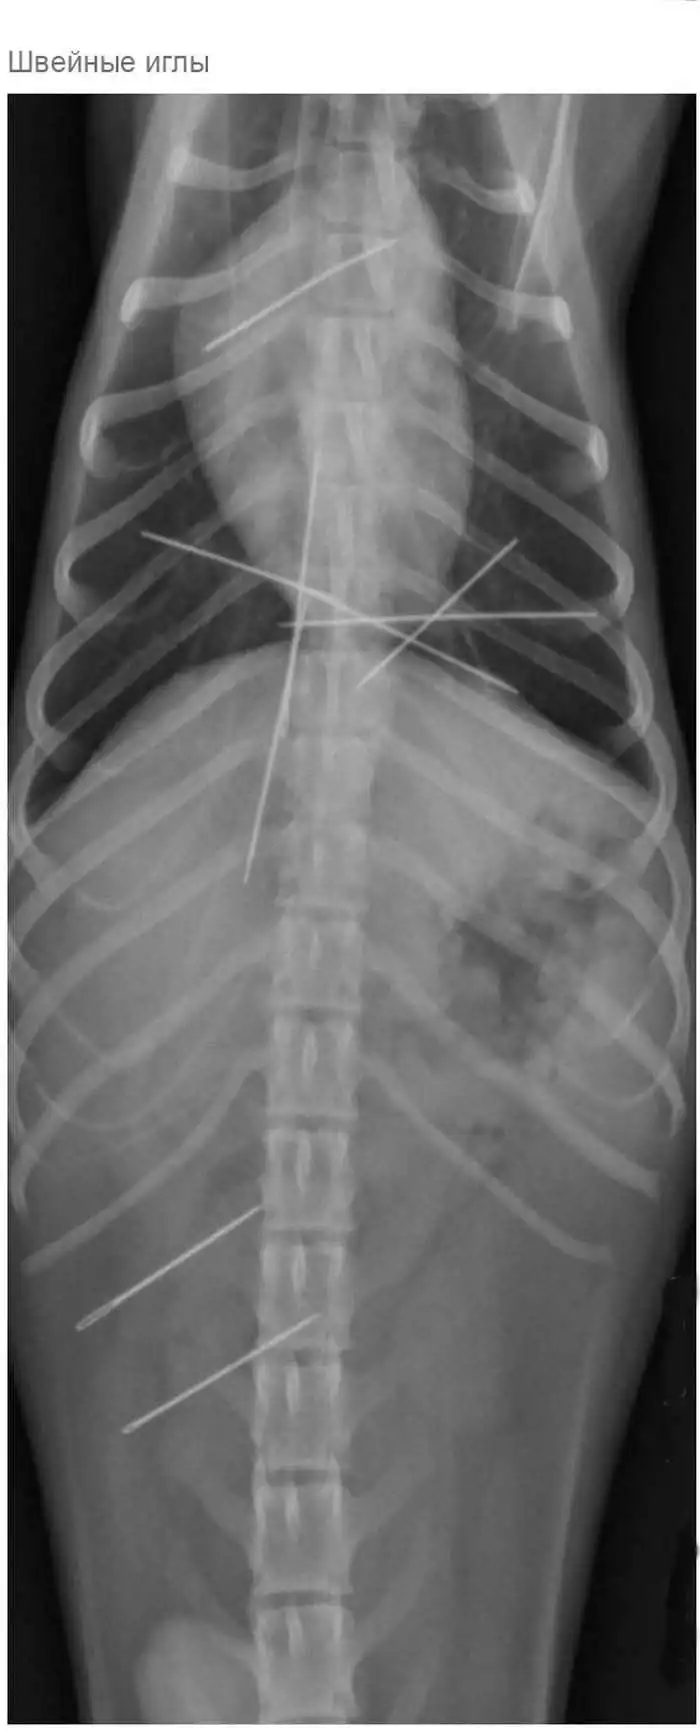

Что может оказаться в желудке собаки

Думаю, всем собачникам известно, что порой у собак бывают такие заскоки, когда они в прямом смысле слова жрут все подряд.